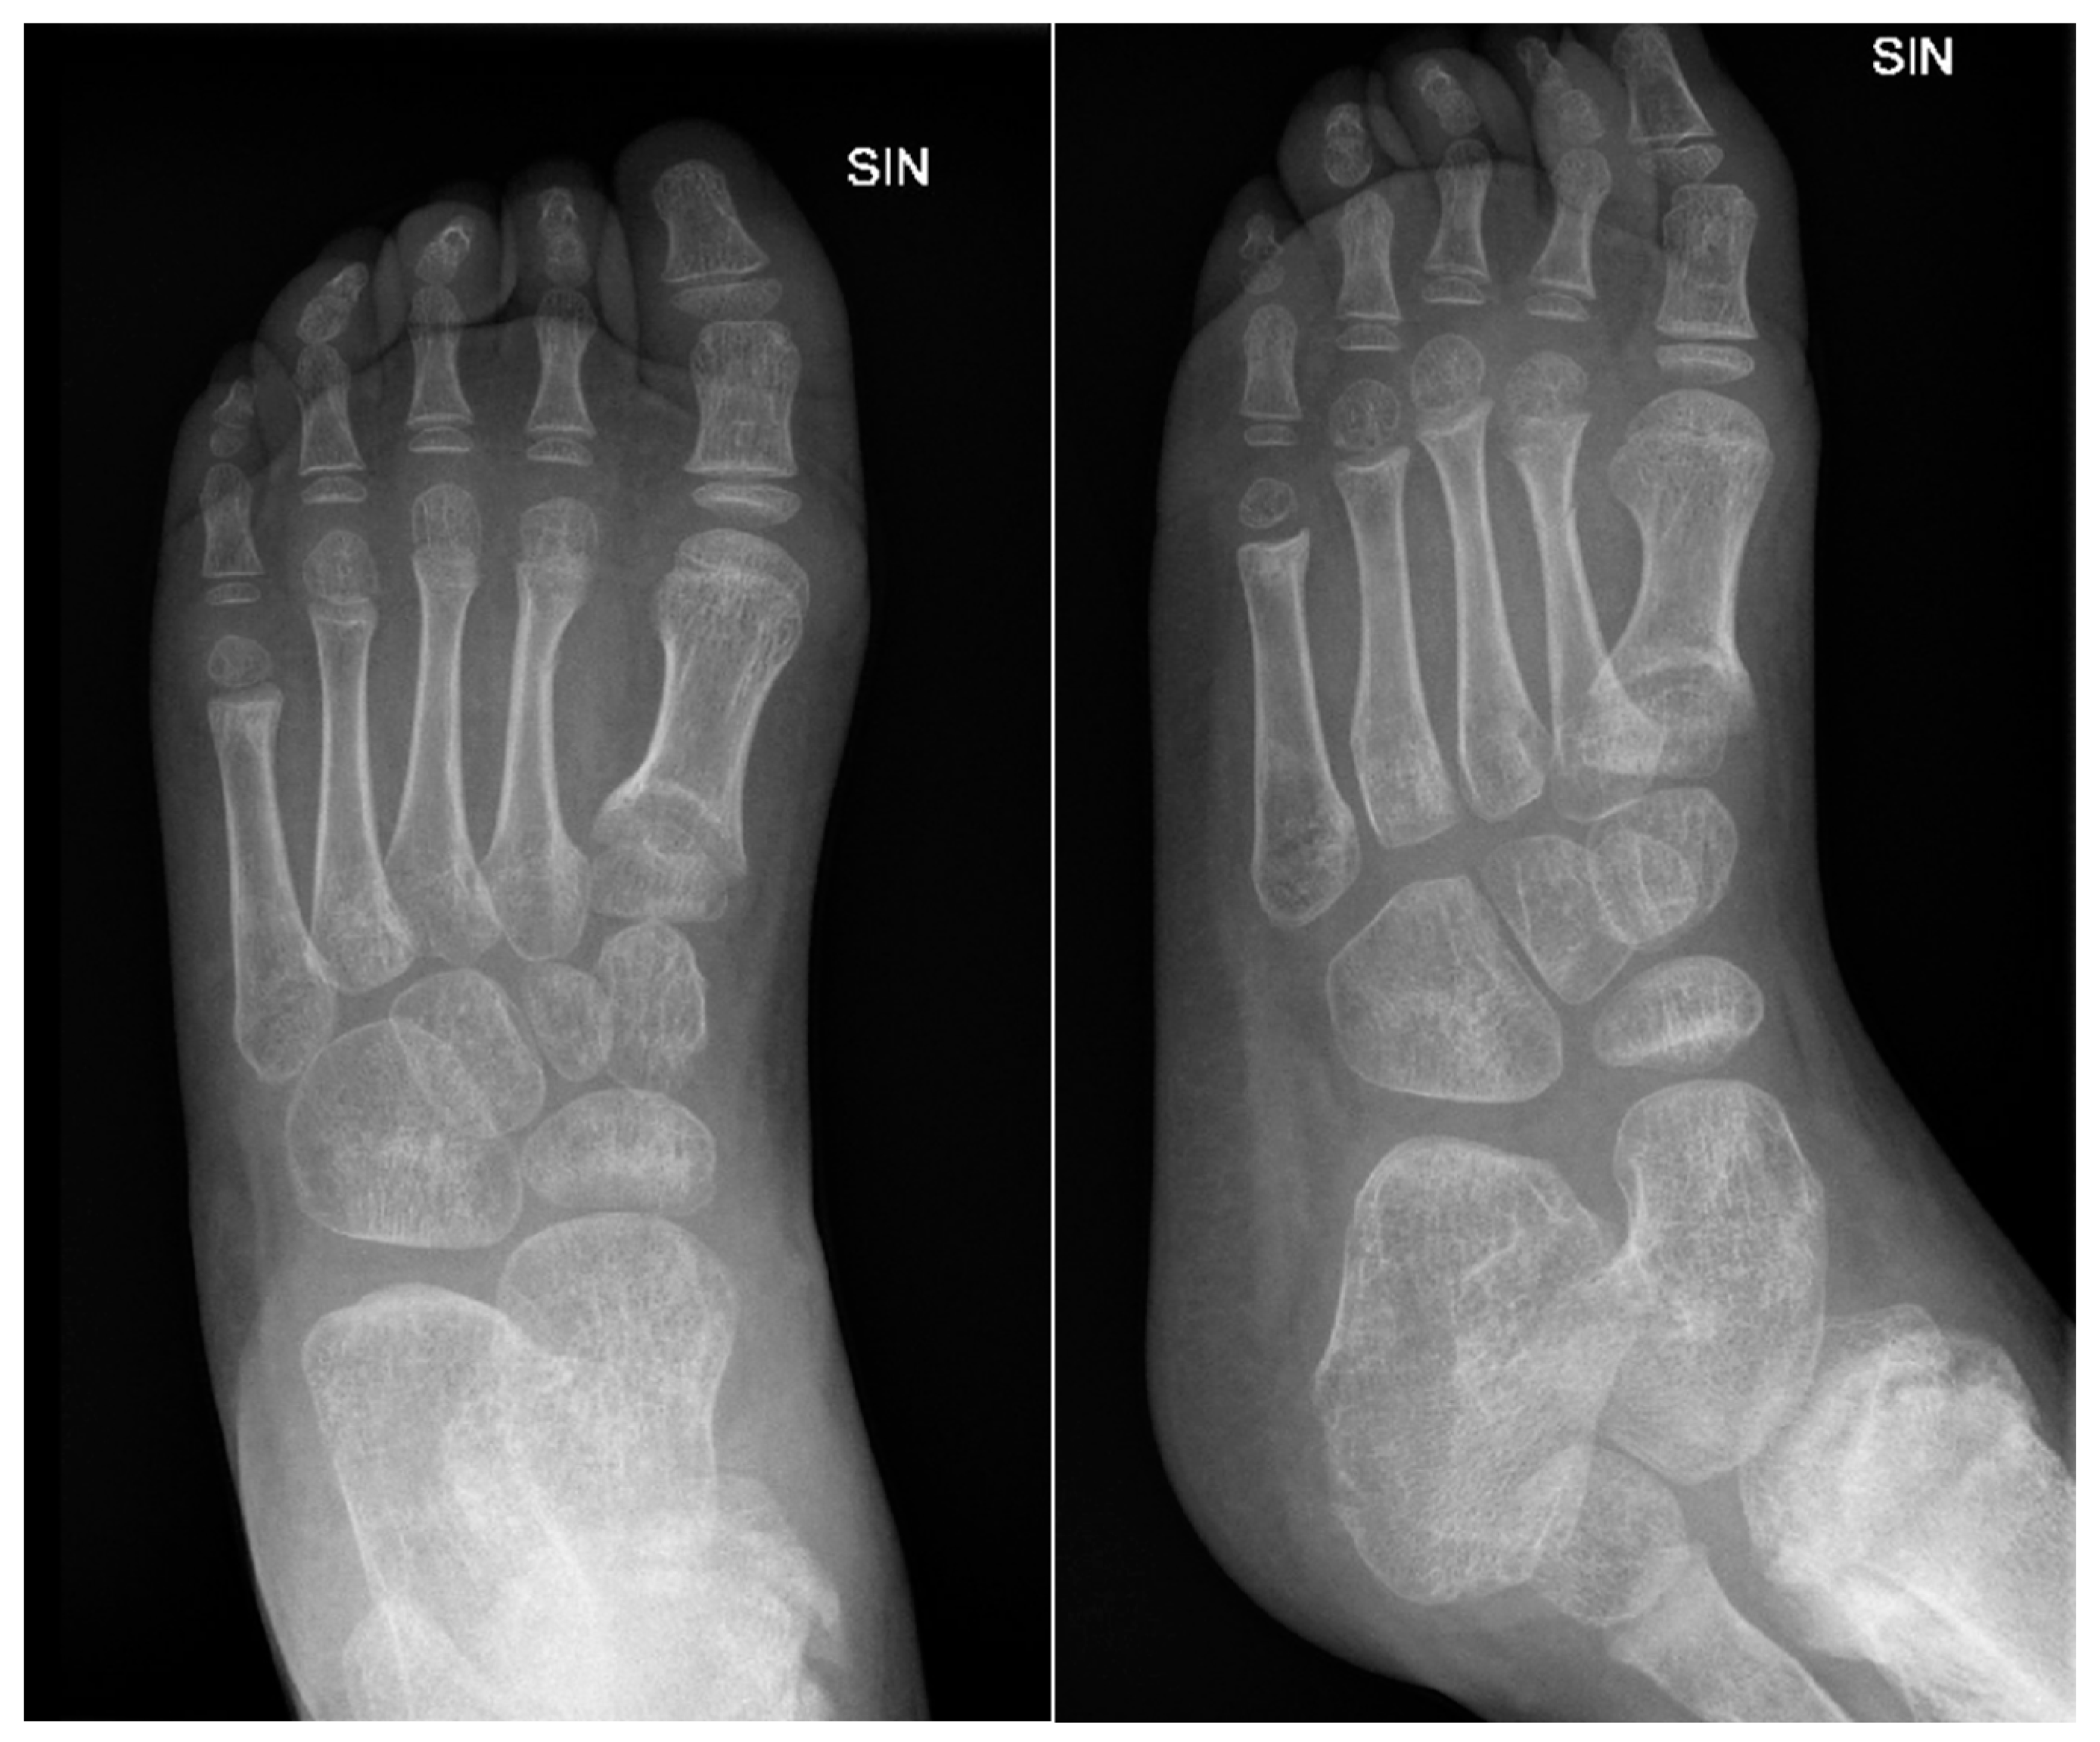

Figure 15. The X-ray examination of the left hip joint, femur and knee joint in AP and lateral projections shows a small, heterogeneous lateral condyle of the femur, a lytic zone in the metaphysis, massive calcification in the mid-diaphysis, normal hip joint gap, smooth surfaces, and no pathologies in the hip joint bones.